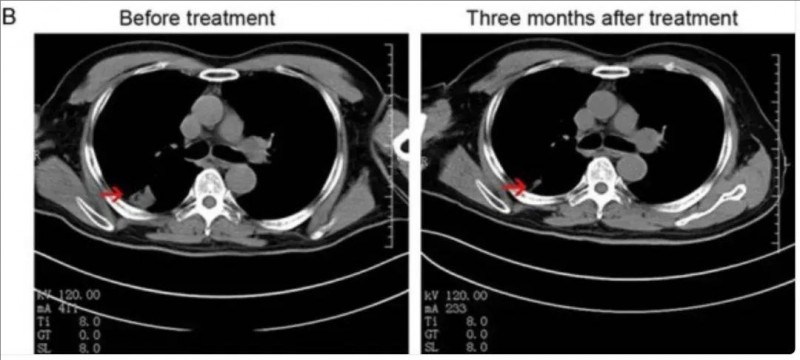

值得一提的是,NK细胞联合治疗组有一位53岁的IVA期非小细胞肺癌男性患者,在治疗3个月后,获得部分缓解(PR),CT扫描显示:右肺肿瘤病灶显著缩小,从治疗前的3.5×3.5cm缩小至1.7×1.3 cm(详见下图)。

▲图源“Am J Cancer Res”,版权归原作者所有,如无意中侵犯了知识产权,请联系我们删除